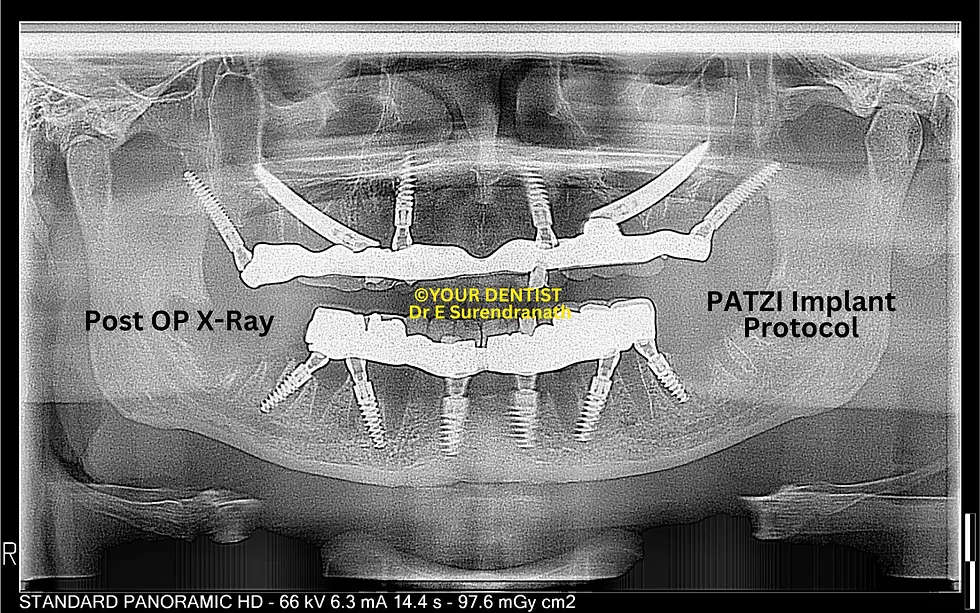

the speciality if your dentist dental hospital is that we not only deal with normal all on 4 and all on 6 but also deal with patients who has less bone or no bone at all...so many people who are rejected for implants elsewhere can come to us for advanced implant options for highly resorbed jaw bones like PATZI protocol or all on 6 with zygomas or quad zygomas and many more options like basal, screw retained basal,or compressive multiunit implants and so on...infact we have a record of not rejecting a case even in utmost resorbtion cases we even opt for patient specific implants.

At YOUR DENTIST Vijayawada, full mouth implant solutions are customized using techniques such as All-on-4, All-on-6, zygomatic implants or pterygoid implants (if needed), or basal implants, or advanced combinations, depending on bone condition.